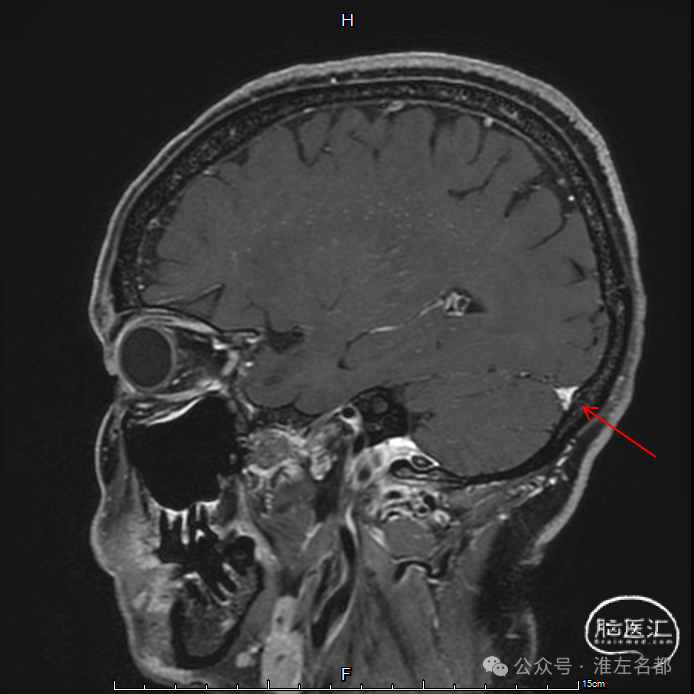

三维黑血高分辨T1

三维黑血高分辨T1平扫(上图)和增强(下图):上矢状窦慢性血栓;直窦内新进血栓(急性血栓等低信号,或亚急性血栓高信号,无强化)。